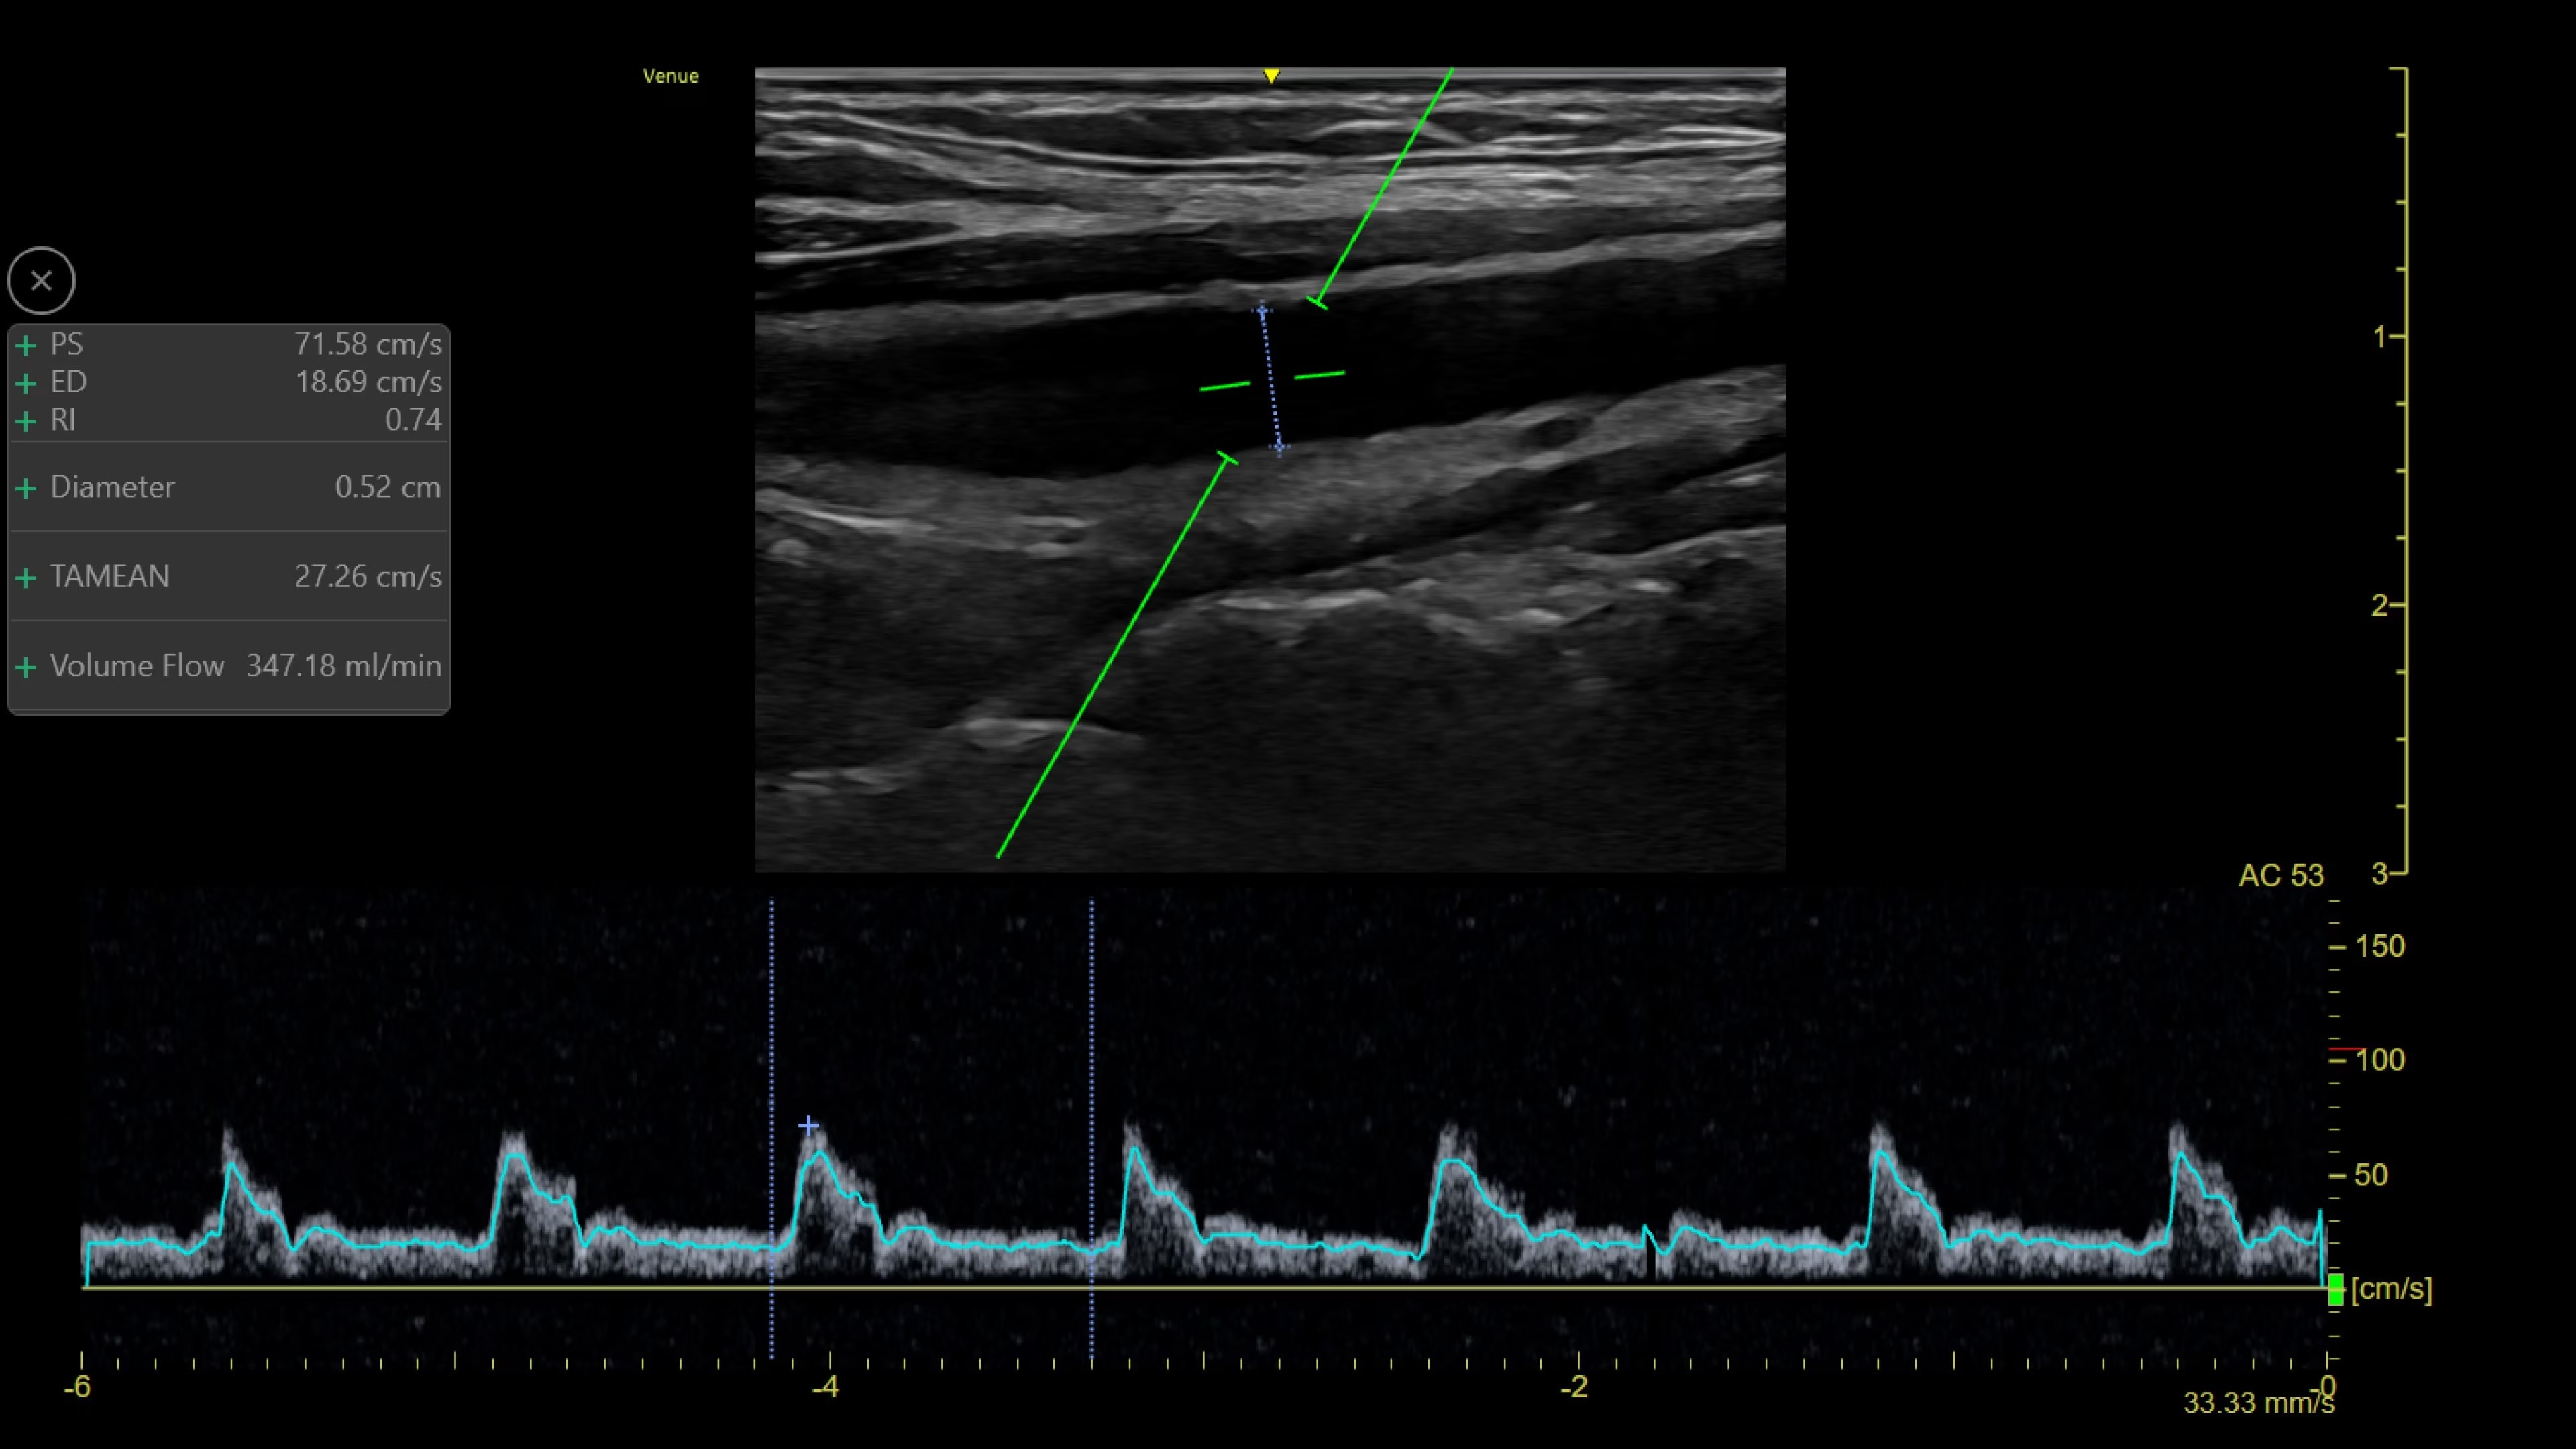

Catheter to Vessel Ratio

Accurate catheter selection tool

Selecting the wrong sized catheter can lead to catheter related thrombosis.2 Catheter to Vessel Ratio is a measurement tool that supports clinicians in selecting the appropriate sized catheter based on vessel diameter.